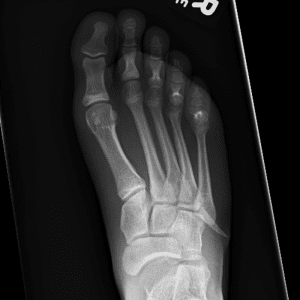

Pediatric Radiographs